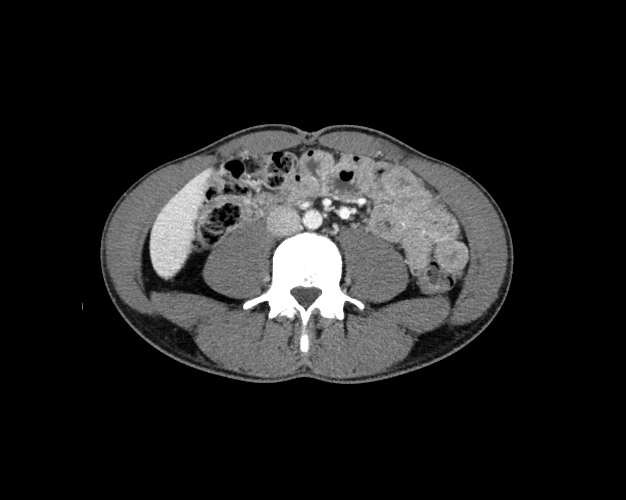

Body

Covers abdominal CT anatomy.